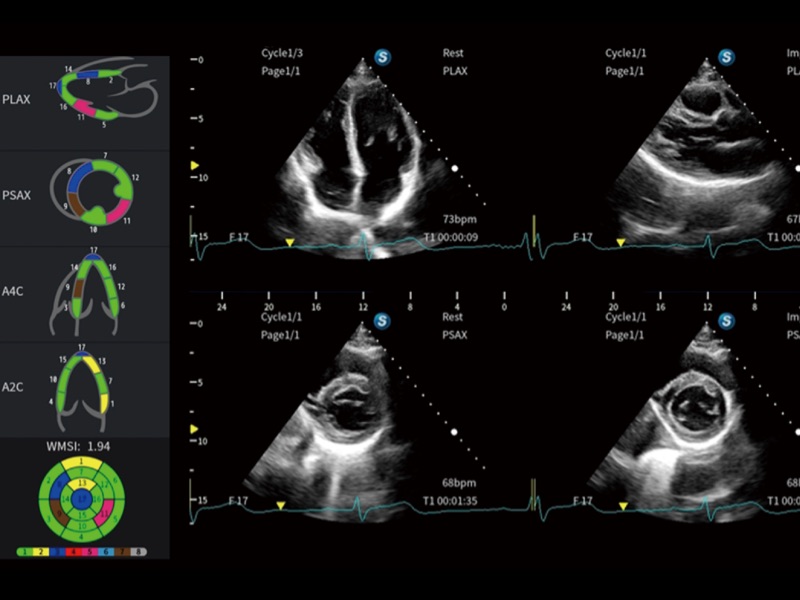

便携式彩色多普勒超声诊断系统

作为开立医疗全新打造的高端全域笔记本超声,X11集成了当前先进的硬件架构和精密的设计工艺,提升多科室临床医生在常规影像检查中的诊断能力,为临床提供全面的诊疗支持。